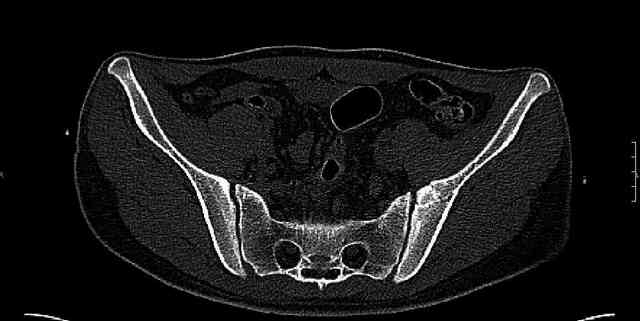

The joint is non-concentric as the head appears to be either "following the caudal segment", or the dome component is displaced from the tethered head... or so it seems... and he's young... so, many fracture surgeons would recommend reduction and fixation.

So we must decide preoperatively which part is the displaced segment?

It's difficult to know from these few selected images which component of the injury (was before and now) should be deemed the "soon to be mobile"

segment. It's my best guess that it is the caudal portion and there exists a healing fracture line somewhere thru the posterior column...one image

suggests it. If true, its early healing/union should be disrupted, and the resultant fragment mobility then allows accurate reduction.

Some more images. Does it help to guess which part of the acetabulum is displaced?

Normal appearing SI joints and a healed posterior column limb... my bet's on caudal segment displacement.